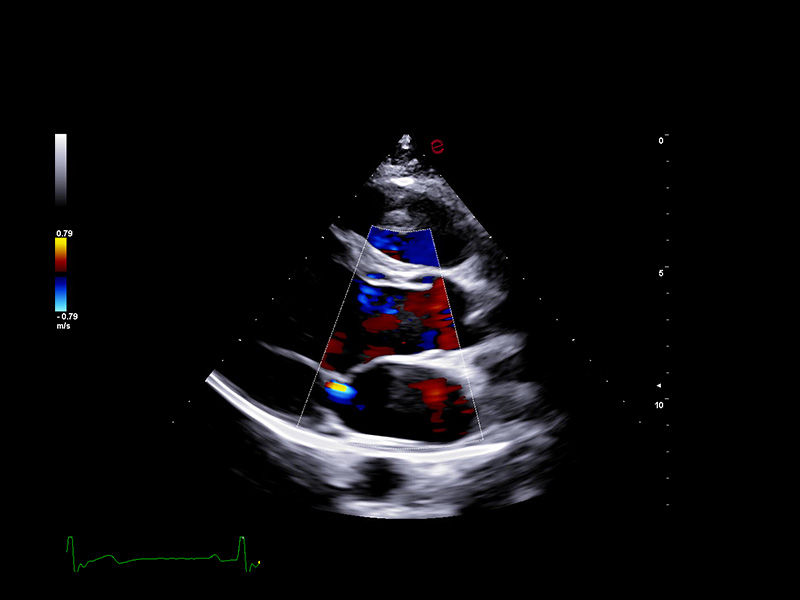

Esaote’s XCrystal probe PX1-5 delivers exceptional clarity in B-mode imaging, providing deep penetration and excellent resolution even in technically challenging patients. Its advanced architecture ensures high Doppler sensitivity and spatial detail, enabling an accurate assessment of wall motion, valve morphology, and flow dynamics. From subtle endocardial borders to low-velocity diastolic flows, the PX1-5 probe ensures you never miss the details that matter.

Esaote’s HyperDoppler technology provides an advanced visualization of intracardiac blood flow dynamics, offering clinicians an intuitive understanding of complex hemodynamics that goes beyond conventional Doppler imaging. By generating real-time vector maps, streamlines, and vortex formations, HyperDoppler enables the detailed assessment of diastolic function, ventricular dyssynchrony, and valvular abnormalities.

This unique flow visualization supports earlier detection of subtle dysfunction and increases diagnostic confidence, particularly in challenging cases such as heart failure, prosthetic valve evaluation, and structural heart disease. HyperDoppler’s zero-click, visually rich interface enables faster, more comprehensive exams, allowing cardiologists to make more informed clinical decisions.